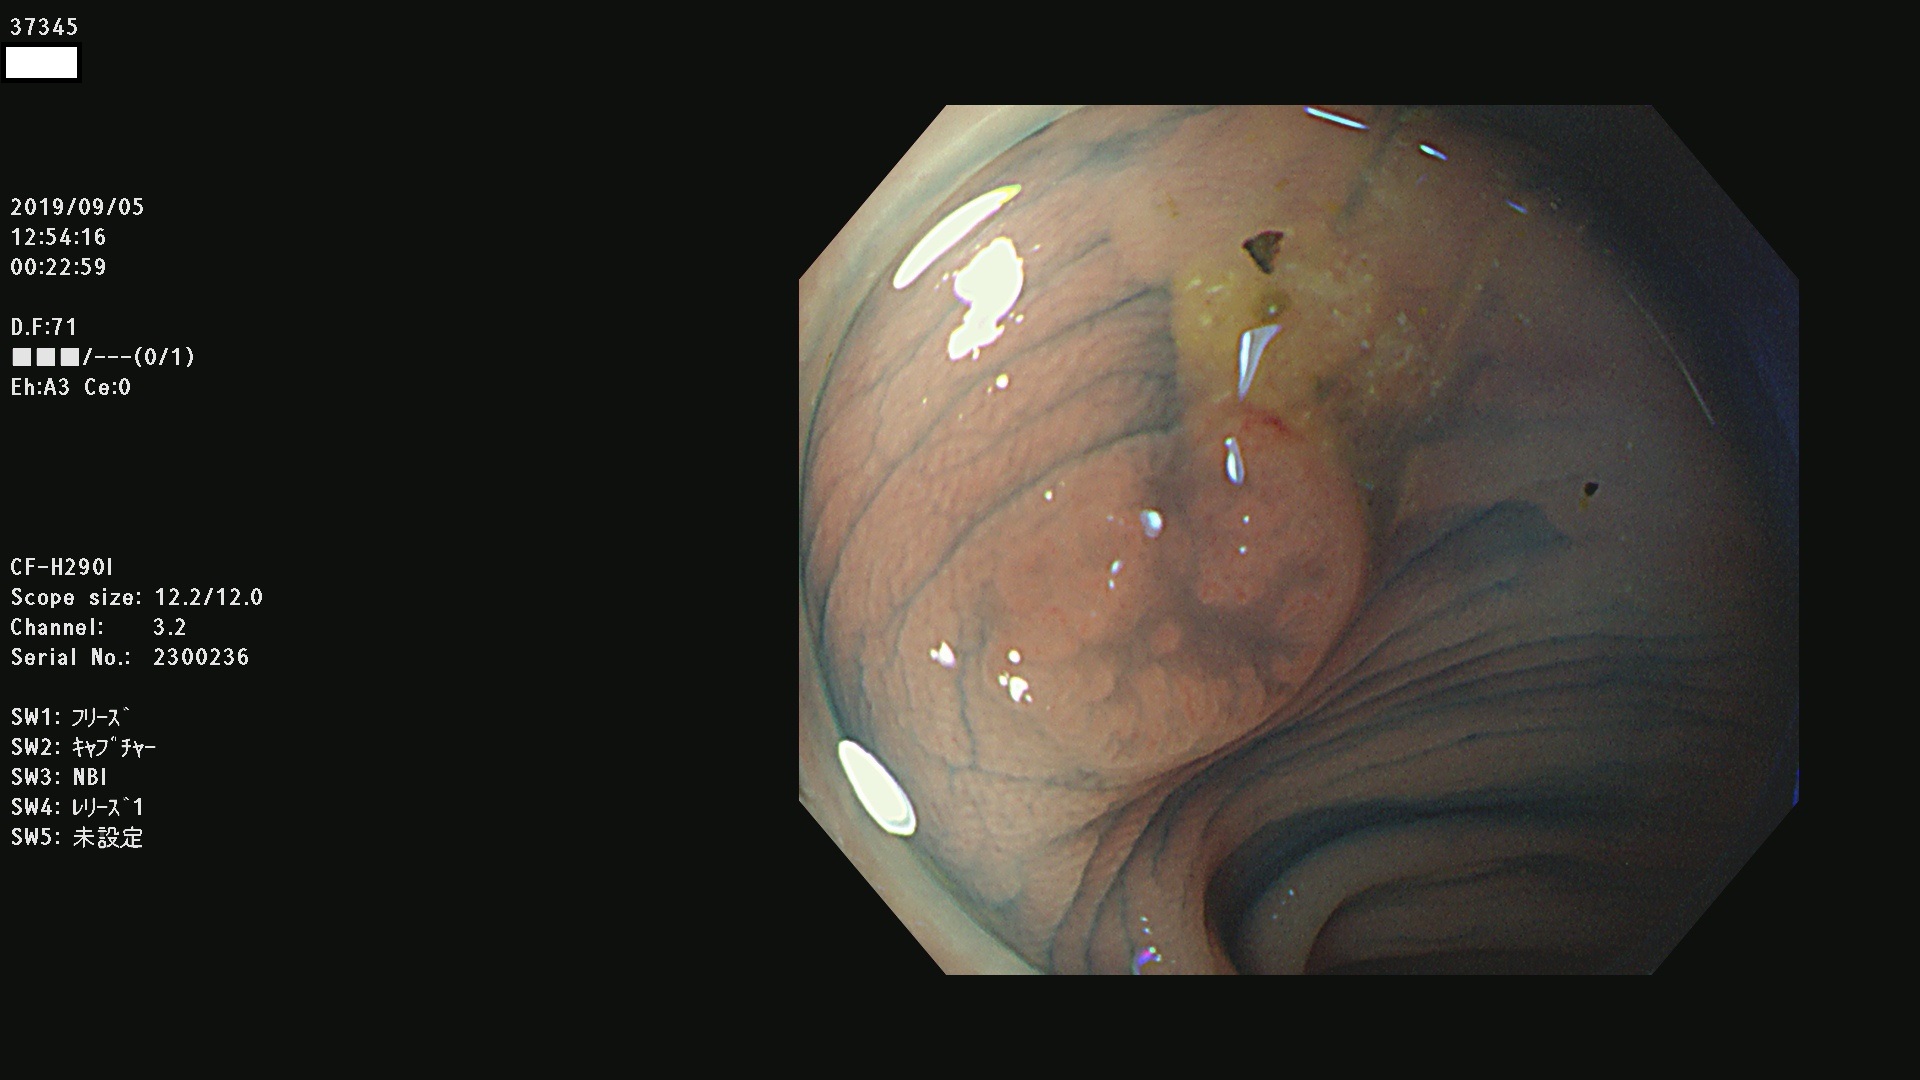

37300(SSAPのみ) 37301 37303 37304 37306 37307 37308 37309 37312 37313 37315(SSAPのみ) 37316 37317(SSAPのみ) 37319 37321(SSAPのみ) 37322 37323 37324 37325 37326 37328(SSAPのみ) 37329 37330 37331 37332(SSAPのみ) 37333 37334 37336 37337 37338 37340 37342 37343(SSAPのみ) 37344 37345 37346 37347 37348 37352(SSAPのみ) 37353 37354 37355 37356 37358 37360 37361(SSAPのみ) 37362 37363 37366 37367 37369 37370 37371 37372(SSAPのみ) 37375 37376 37377 37380 37381(SSAPのみ) 37382 37383 37384 37385(SSAPのみ) 37386 37387 37388 37389 37390 37392(SSAPのみ) 37393 37394 37395 37396(SSAPのみ) 37397 37398(SSAPのみ) 37399

発見困難で危険性の高い平坦型病変(上記100名より抽出) )